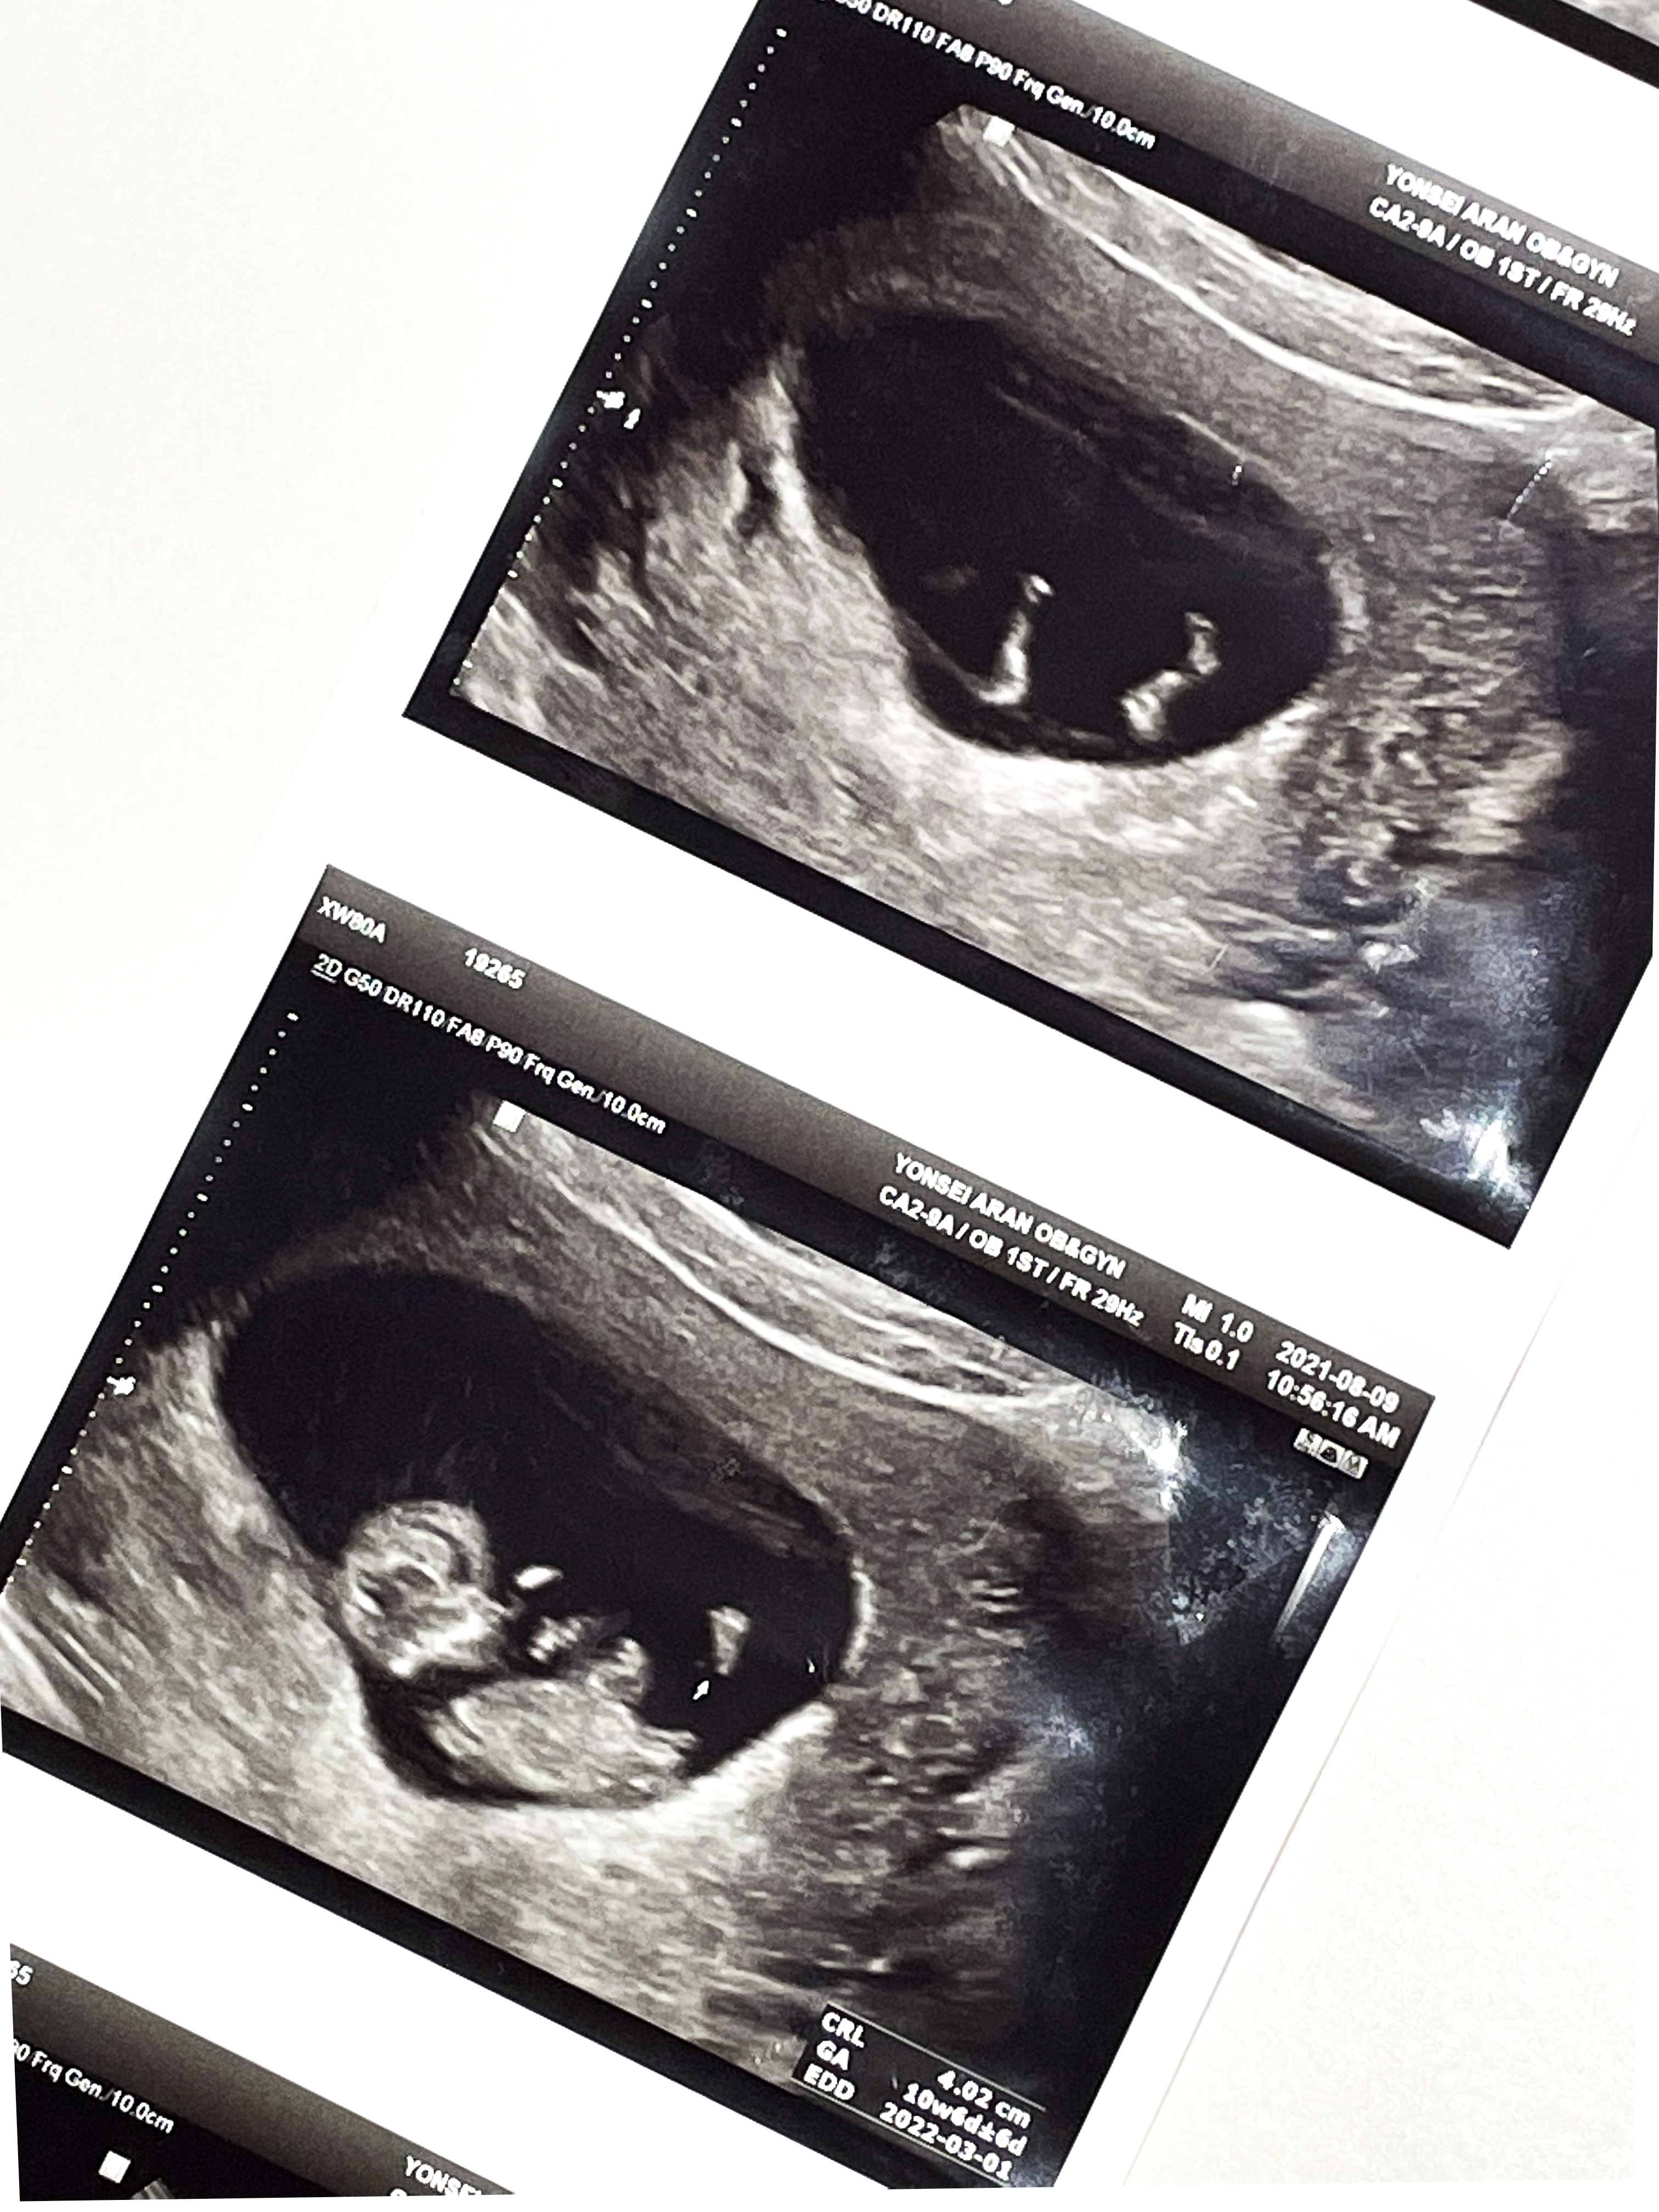

입덧약 처방 받으러 간 김에 초음파도 한 번 봤다.

막대기 같이 생겼던 아기가 어느덧 통통해졌고 팔다리까지 있었다.

쌤이 젤리곰이라고 너무 귀엽다고 하셨는데,

내 눈에는 물개 같았다.

심장도 잘 뛰고 있었다.

뇌 쪽이 구멍이 뚫려 있었는데 정상이라고 하셨다.

벌써 배초음파를 볼 수 있었다.

2주사이에 배도 더 통통해지고

코도 보였다.

쌤이 코가 높다고 해주셔서 기분이 좋아졌다.

발바닥도 보인다고 찍어주셨는데

발바닥이 넘나 귀여웠다.

팔다리도 길쭉 해지고,

아주 기특하게 잘 자라고 있었다.